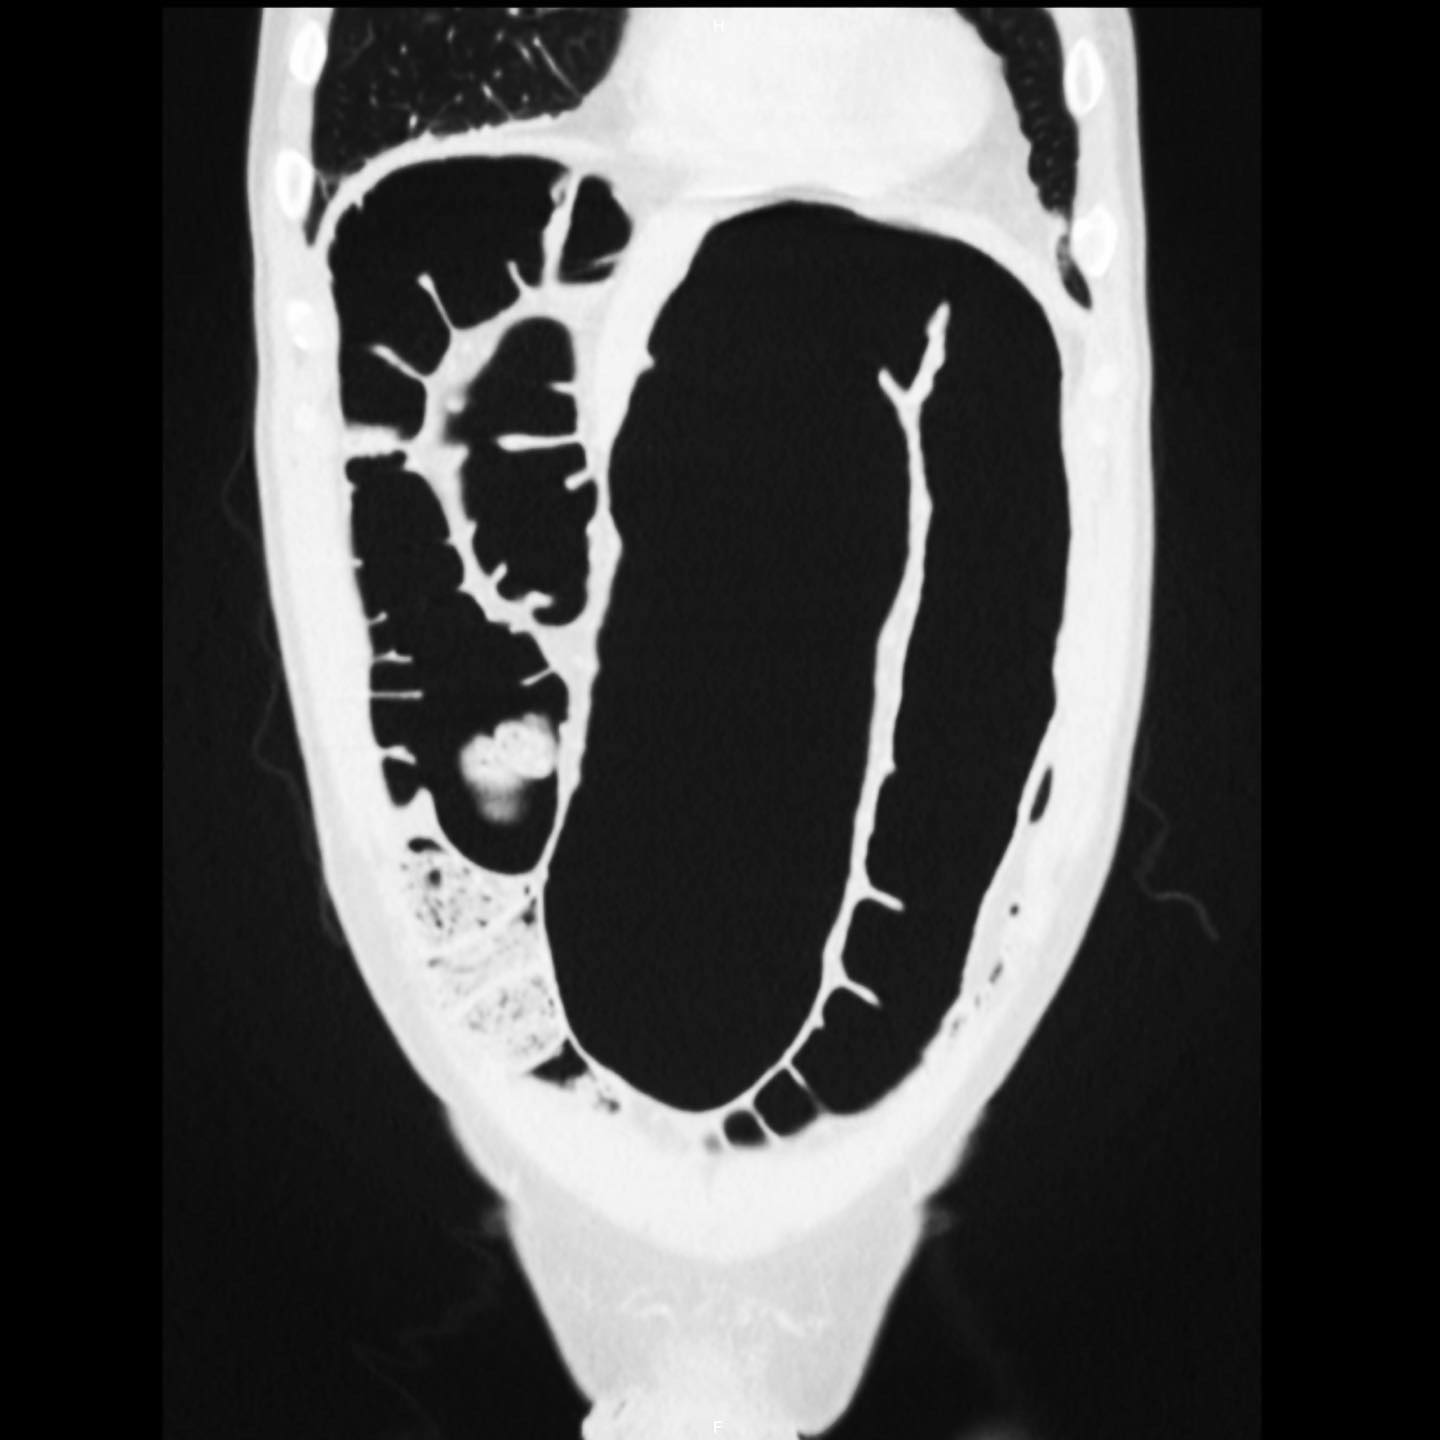

TAC de abdomen presencia de divertículos en colon sigmoides

Colon por enema, cáncer colón, diverticulitis Enema opaco de doble